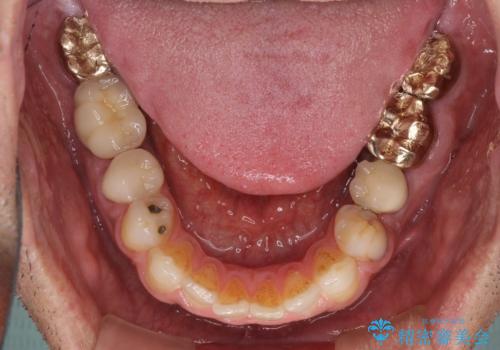

抜歯が必要な左右の奥歯 ブリッジとインプラントによる奥歯の補綴治療

- 咬んだときに奥歯に痛みを感じるとのことで来院された患者様です。

診査の結果、左側は奥歯2本、右側は1本の抜歯が必要であることが分かりました。

左側は大臼歯2本と小臼歯1本が欠損しているため、インプラント2本を治療したブリッジ、右側は中間欠損であり、前後の歯も加療が必要であったためブリッジによる補綴治療を行うこととしました。

抜歯となった歯は全て神経が抜かれた歯であり、強大な咬合力によって破折したことが原因で抜歯となりました。